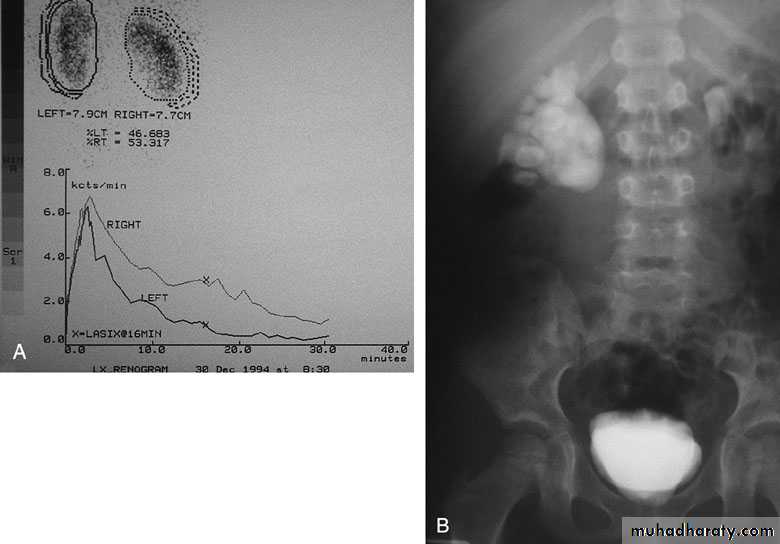

Ureteropelvic Junction (UPJ)(PUJ) Obstruction (stenosis)

The most common cause of significant dilation of the collecting system in the fetal kidney

Boys > Girls

Left-sided lesions predominate

15% bilateral

SYMPTOMS/PRESENTATION

Most infants are asymptomatic and most children are discovered because of their symptoms

Episodic flank or upper abdominal pain, sometimes associated with nausea and vomiting

DIAGNOSIS

U/S: hydronephrosis

IVU: diagnostic , hydronephrosis with

fixed stenotic segment or complete

obstruction

CT scan: hydronephrosis that ends

abruptly

Magnetic Resonance Imaging

Radionuclide Renography: to see the

split function of each kidney

Pressure-Flow Studies: Whitaker test